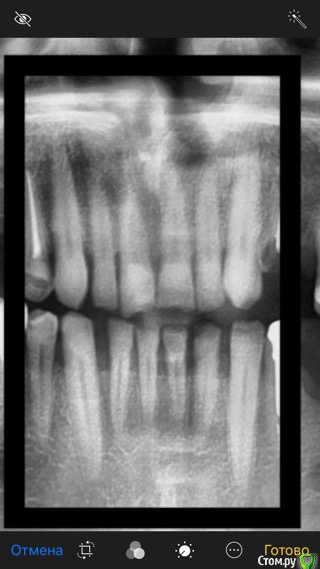

ramzes20091 Опубликовано 15 февраля, 2019 Поделиться Опубликовано 15 февраля, 2019 Хотел бы изучить возможность привода в порядок передних зубов путем современного композитного послойного восстановления, виниры и прочие нанониры пока не рассматриваю из за морального и материального истощения после имплантации) Верхние резцы не крошатся-это очень давнишняя травма... Ссылка на комментарий

kramer Опубликовано 15 февраля, 2019 Поделиться Опубликовано 15 февраля, 2019 Я бы сначала разобрался с причиной генерализованной стираемости зубов... Ссылка на комментарий

ramzes20091 Опубликовано 15 февраля, 2019 Автор Поделиться Опубликовано 15 февраля, 2019 Практически не было жевательных зубов-сейчас проблема устранена путем имплантации и выравнивания прикуса. Ссылка на комментарий

DmitrySH Опубликовано 15 февраля, 2019 Поделиться Опубликовано 15 февраля, 2019 Хотел бы изучить возможность привода в порядок передних зубов путем современного композитного послойного восстановления, Так себе идея, очень ненадежный путь. Ссылка на комментарий

DmitrySH Опубликовано 16 февраля, 2019 Поделиться Опубликовано 16 февраля, 2019 Как вариант, временно поправить только 2 верхних центральных резца пломбировочным материалом (но быть готовым к сколам) и накопить на виниры Ссылка на комментарий

ramzes20091 Опубликовано 16 февраля, 2019 Автор Поделиться Опубликовано 16 февраля, 2019 Спасибо) я так и подумал-отбелить и сделать пока верх композитом... Думаете виниры подойдут? в одном месте сказали-только коронки! виниры не подойдут, причину-не объяснили... Ссылка на комментарий

DmitrySH Опубликовано 16 февраля, 2019 Поделиться Опубликовано 16 февраля, 2019 Думаете виниры подойдут? в одном месте сказали-только коронки! виниры не подойдут, причину-не объяснили... На этот вопрос по интернету не ответить Ссылка на комментарий